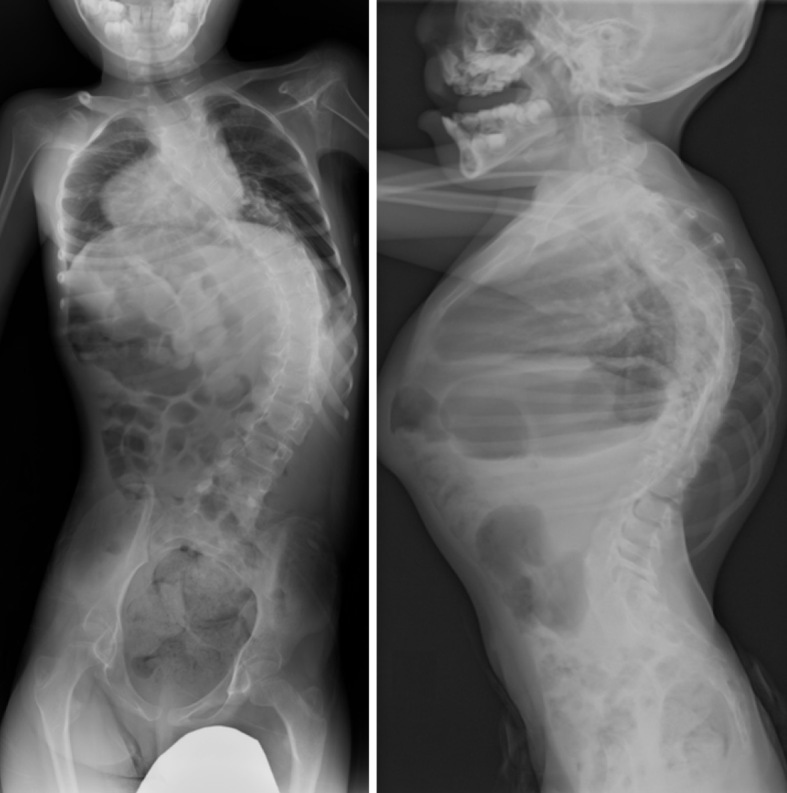

A Case of Early Onset Scoliosis with Trisomy 1q and Monosomy 21q.

Abstract Image